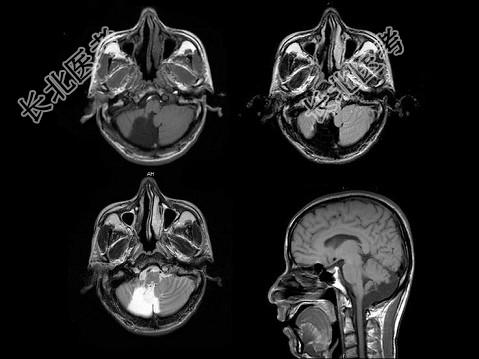

- 单项选择题男,45岁, 共济失调伴癫痫发作,结合图像, 最可能的诊断是 ( )

A、脑干畸形

B、胼胝体发育不良

C、脑室畸形

D、Chiari畸形

E、Dandy-Walker综合征